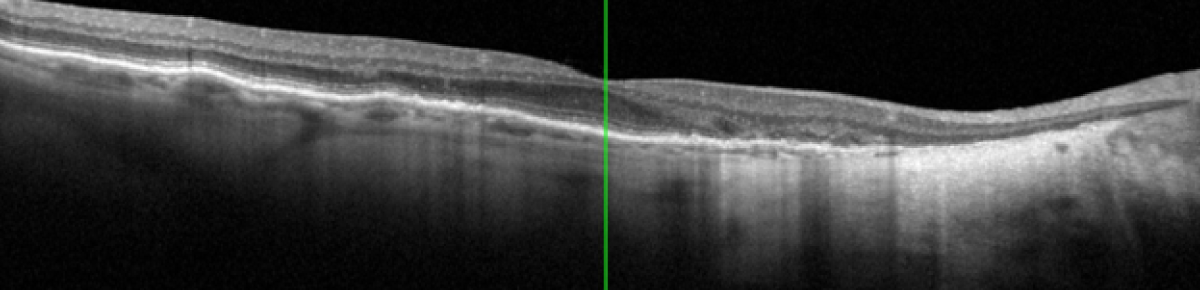

Cette formation e-learning est dédiée à l'examen d'OCT (Tomographie par Cohérence Optique), un outil incontournable dans l'exploration et le suivi des pathologies rétiniennes. Elle a pour objectif de fournir une compréhension complète et pratique de l'examen, depuis ses principes fondamentaux jusqu'à sa réalisation et son suivi.

La formation débute par une présentation de l'OCT, permettant de comprendre son fonctionnement, ses principes technologiques et son intérêt clinique. Elle aborde ensuite les indications de l'examen, en précisant dans quelles situations l'OCT est recommandée et quelles informations il permet d'obtenir.

Un chapitre est consacré à la réalisation de l'examen, avec un focus sur la préparation du patient, le déroulement pratique, les bonnes pratiques et les points de vigilance afin d'obtenir des images de qualité.

Enfin, la formation traitée de l'après-examen, incluant l'analyse de la qualité et du rapport obtenu afin de transmettre des examens fiables à l'ophtalmologiste.

Comprendre les principes et l'intérêt clinique de l'OCT

Identifier les principales indications de l'OCT en fonction des pathologies et des situations cliniques

Réaliser un examen d'OCT dans de bonnes conditions

Obtenir un examen fiable et interprétable par l'ophtalmologiste